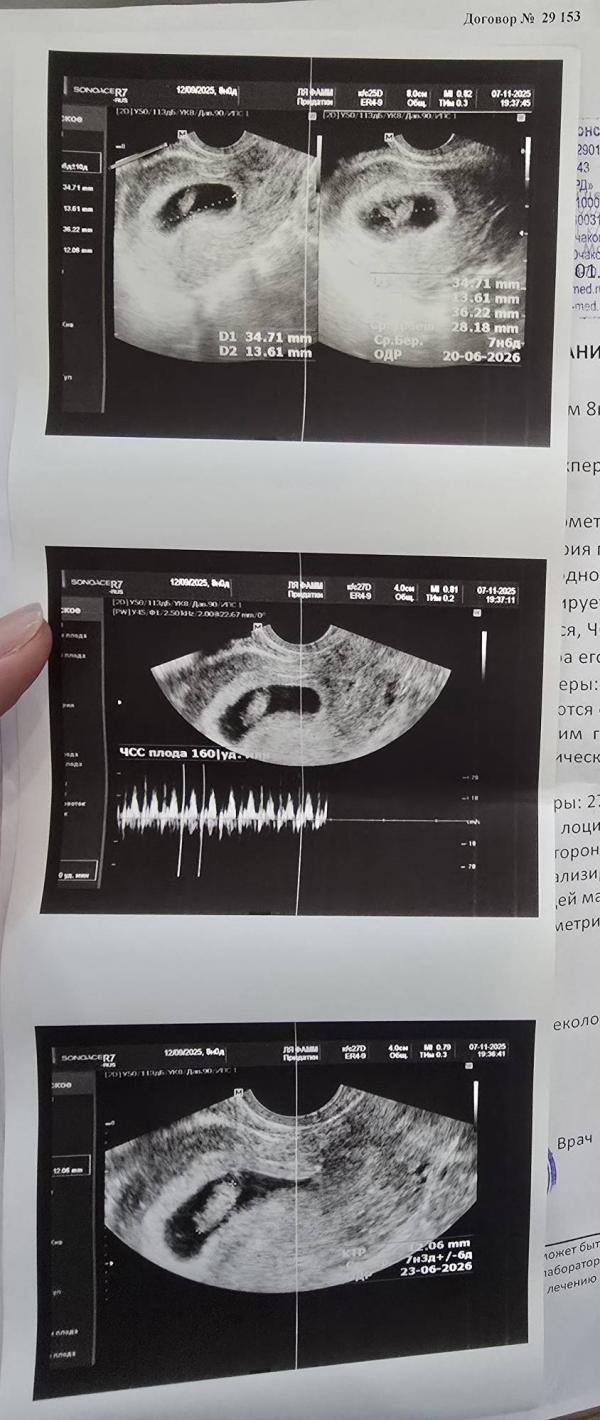

Первое узи маленького эмбриончика, предварительно подтвердили срок, сердечко бьётся 160 чсс❤️ и всё хорошо *тьфу тьфу тьфу😁*